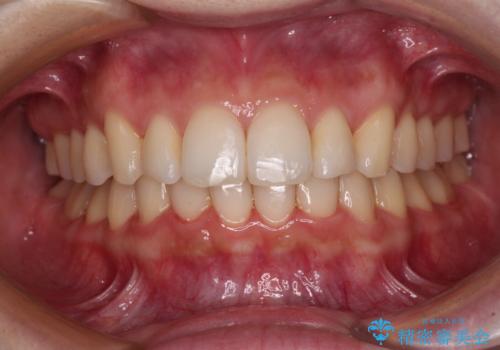

矯正治療の後戻り ガタガタになった前歯の部分矯正

- 以前の矯正治療の後戻りを気にして来院された患者様です。

下顎前歯にデコボコがあるため、ワイヤー矯正により改善することとしました。

もう少しデコボコを改善したかったのですが、ご本人の希望もあり、装置を除去しました。

後戻りを防止するため、舌側を細いワイヤーによる保定を行いました。